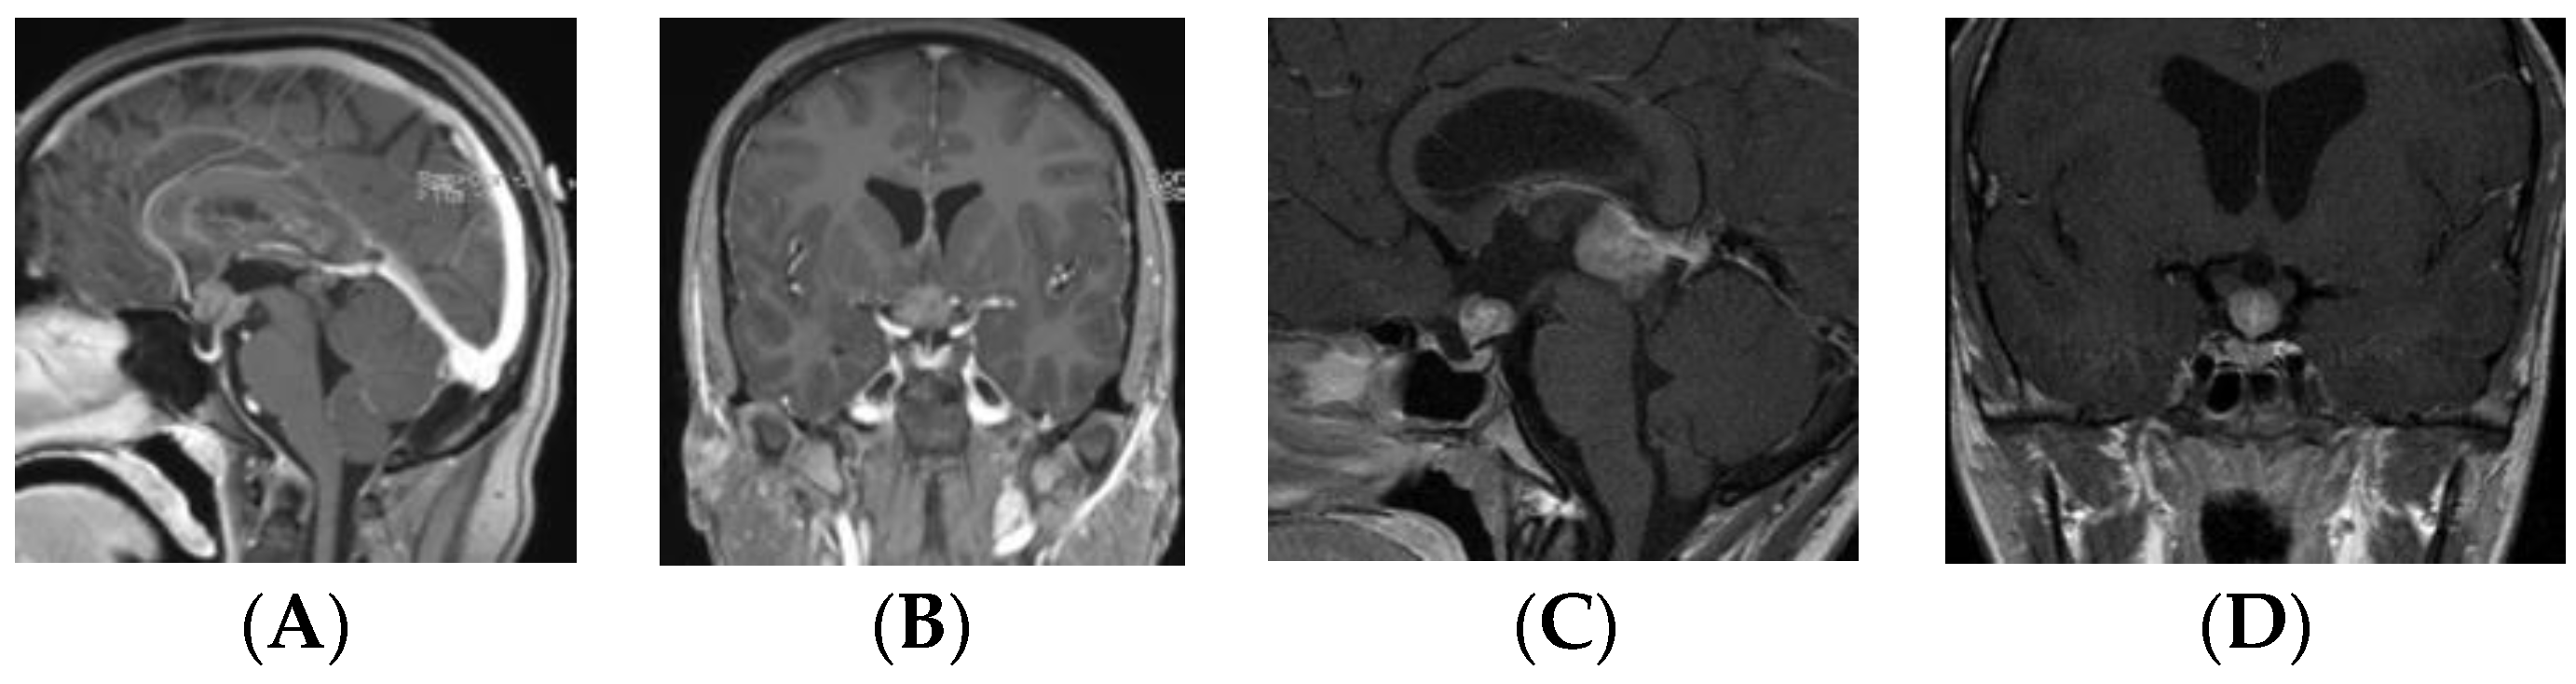

• Type Ia: Globular anterior III ventricle lesion with identifiable PS and PG (Figure 1);

• Type Ib: Globular anterior III ventricle lesion without identifiable PS but with identifiable PG (Figure 2);

Figure 1. Type Ia. Post-contrast MR, sagittal (A) and coronal (B) views of a patient with suprasellar germ cell tumor (S-GCT) and post-contrast MR, sagittal (C) and coronal (D) views of a patient with bifocal GCT. Note an anterior third ventricle tumor with preserved pituitary stalk and gland.

Patients in the S-GCT group skewed toward masses of the anterior III ventricle. Of 22 S-GCTs: seven were Type Ia or Ib (Figure 1 and Figure 2), seven were Type II (Figure 3), and six were Type III (Figure 4). These 20 S-GCTs were all globular appearance. In four patients (two each of S-GCT Type II and III), the tumor extended laterally into the cavernous sinus (Figure 3C,D; Figure 4C,D). Each of these patients presented with cranial nerve dysfunction. The two non-globular S-GCTs were small and confined to the PS (Types IV and V).

By contrast, the majority (11/16, 68.8%) of bifocal GCTs were smaller and Type IV (Figure 5). These tumors were accompanied by much larger pineal region tumors. Four bifocal tumors were Type Ia or Type Ib tumors with similarly sized globular masses in the suprasellar and pineal regions. 1 patient had a Type II mass with extension of the tumor directly into the sella turcica.